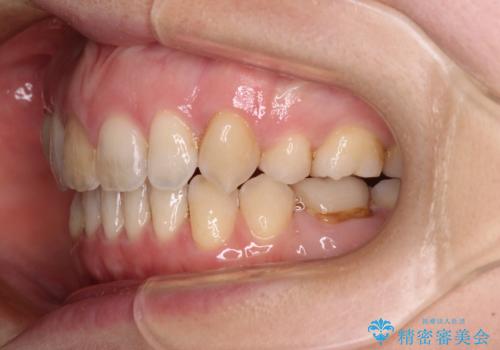

上下の前歯に隙間が空くほど上顎前歯が前に飛び出していましたが、抜歯矯正により上下前歯がぴったりと付くほど口元を引っ込めることができました。

上顎左右第一小臼歯2本、下顎左右第二小臼歯2本を抜歯し、ワイヤー装置にて口元を引っ込めるよう矯正治療を行うこととしました。